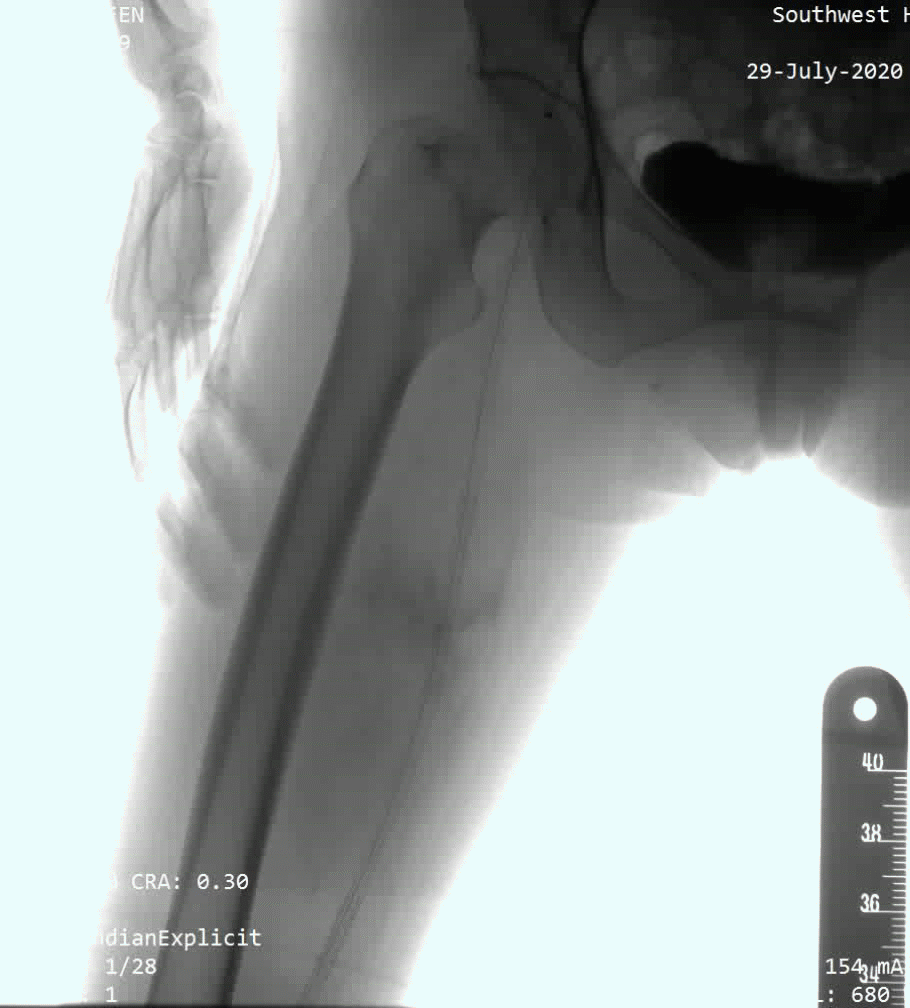

病例2为股浅长段CTO病变,术中多次尝试,开通极其困难,使用Connect Flex导丝后顺利通过闭塞段。Command 18+Connect flex的导丝组合能处理大部分CTO病变

Command 18+Connect flex的导丝组合,融合了这两款导丝的特性,包括强支撑力、耐久性、高穿刺能力、优秀的可控性等特点,能处理临床上的大部分CTO病变。另外,对于部分正向开通困难,如严重钙化,或病变位置不利于正向开通,如髂总开口病变,合理使用逆向导丝技术非常重要。病例3为Command 18联合Connect flex导丝顺利治疗的髂开口闭塞合并股浅长段CTO病变;术中首先采用逆向技术,穿刺股总动脉,开通髂动脉;随后使用Connect flex导丝顺利开通股浅远端长段CTO病变。